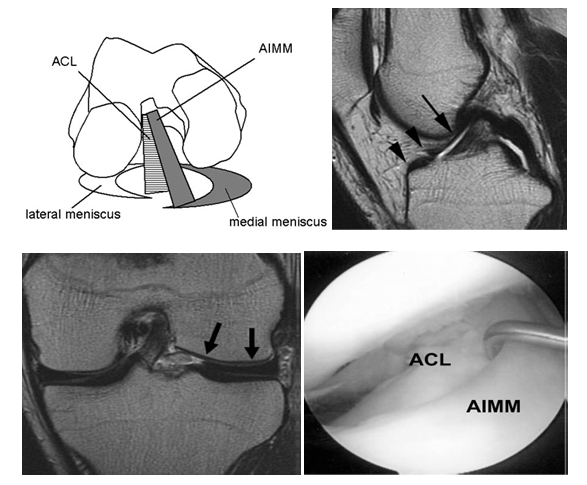

Only a few reports of anomalous insertion of the medial meniscus exist (Figure 5), and they include abnormal insertion of the medial meniscus into the anterior cruciate ligament,6 anomalous insertion of the anterior horn of the medial meniscus into the intercondylar notch of the femur with an absent transverse meniscal ligament7 and a case of an anomalous band in continuity with the medial meniscus that extended from the posterior horn area of the medial meniscus to insert into the mid portion of the anterior cruciate ligament.8 Other anomalies (variants) of the medial meniscus described in the literature include discoid variants, discoid variants associated with a cyst, discoid medial meniscus bilaterally, absent fixation of the transverse meniscal ligament to the tibial plateau, buckled meniscus, hypoplasia of the anterior horn, the posterior horn, the entire meniscus, the ACL, and anomalous attachment of the posterior horn.9 In a morphologic study of 48 cadaveric knees, reported four tibial insertion locations of the medial meniscus. Type I insertions were located in the flat intercondylar region of the tibial plateau; type II occurred on the downward slope from the medial articular plateau to the intercondylar region; type III occurred on the anterior slope of the tibial plateau; and in type IV there was no firm bony insertion of the anterior horn of the medial meniscus. The occurrence for type I was reported to be 59%; type II, 24% ; type III, 15%; and type IV, 3%.10

Figure 5 Anomalous insertion of the medial meniscus (AIMM) anterior into the anterior cruciate ligament,(a) diagrammatic representation,(b,c) MRI showing anomalous insertion,(d) confirmed on arthroscopy.

In an arthroscopic study of variants of the anterior horn of the medical meniscus the authors classified medial meniscus insertion into the following four categories, the ACL (anterior cruciate ligament) type, where the anterior horn of the medial meniscus was attached to the ACL; the transverse ligament type, where the anterior horn of the medial meniscus was attached to the transverse ligament; the coronary ligament type, where the anterior horn of the medial meniscus was attached to the coronary ligament; and the infrapatellar fold type, where the anterior horn of the medial meniscus was attached to the infrapatellar synovial fold.11–16 J-G CHA et al.12 found that the prevalence of a medial discoid meniscus in patients with Anomalous insertion of medial meniscus (AIMMs) on ACL was much higher than reported. Anomalous insertion of medial meniscus on ACL has a closer connection with a medial discoid meniscus than a lateral discoid meniscus [10]. Radiographic findings are uncommon in cases of medial discoid menisci.13,17